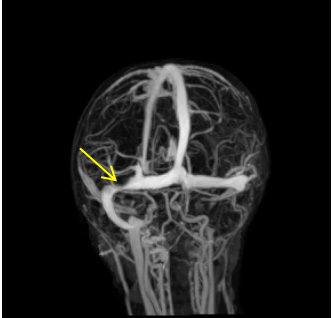

▲ 术前:左侧枕部硬膜外血肿

▲ 术前:血肿压迫横窦

小景年龄较小,硬膜外血肿压迫横窦,再加上她本身是地中海贫血患者,血色素低,术中大出血风险极高。错综复杂的病情,对手术医生的刀上功夫产生了极大挑战。术前曹辉医生积极联系输血科备齐红细胞悬液、新鲜冰冻血浆,术中科主任刘阳主刀,副主任张海、主治医生曹辉分别为一助、二助,三人默契配合,仔细轻柔地清除了脑内血肿,手术过程十分顺利。